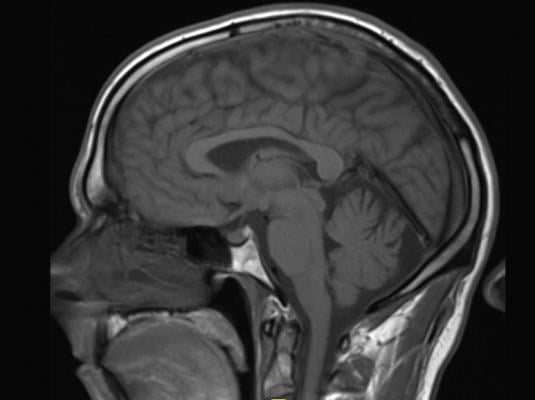

The EMA initiated a review last March of the risk of gadolinium deposition in brain tissue following the repeated use of gadolinium contrast agents in patients undergoing magnetic resonance imaging (MRI) scans.1 After carrying out an almost year-long, in-depth review of the risk of brain deposits and of the overall safety of these products, the PRAC recommendations2 are as follows:

The agents concerned are intravenous injections of gadobenic acid, gadodiamide, gadopentetic acid and gadoversetamide, which are given to patients to enhance images from magnetic resonance imaging (MRI) body scans. (...)

Other agents, known as macrocyclic agents, are more stable and have a much lower propensity to release gadolinium. The PRAC recommends that macrocyclic agents3 be used at the lowest dose that enhances images sufficiently to make diagnoses and only when unenhanced body scans are not suitable.

Some linear agents will remain available: gadoxetic acid, a linear agent used at a low dose for liver scans, can remain on the market as it meets an important diagnostic need in patients with few alternatives. In addition, a formulation of gadopentetic acid injected directly into joints is to remain available because its gadolinium concentration is very low – around 200 times lower than those of intravenous products. Both agents should be used at the lowest dose that enhances images sufficiently to make diagnoses and only if unenhanced scans are not suitable. (...)”